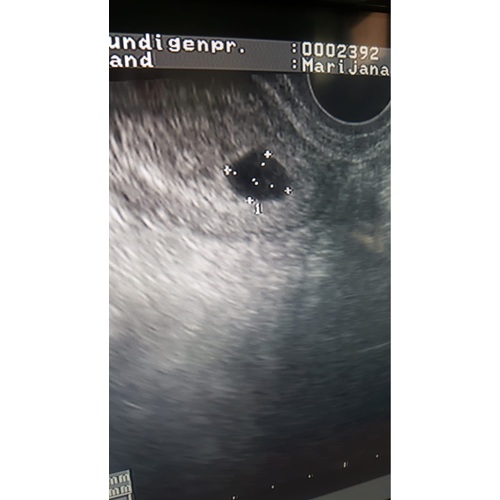

Even een update trouwens, vorige week echo gehad nog en daar zag de verloskundige weer niks, wel was deze gegroeid van 1x1cm naar 1,5x2,5cm... vk verwees me door naar vk in ziekenhuis om te bespreken hoe verder.

Gister bij de verloskundige in het ziekenhuis geweest. Ben in shock. Die verloskundige zag het vruchtje gelijk. Echter was het vruchtje wel zo erg naar de baarmoedermond gezakt en was er geen hartactie te zien dus was er wel een miskraam op gang aan het komen. Maar het feit dat zij zelfs als het vruchtje zo vergaat hem gelijk ziet vind ik bijzonder. Daarnaast was het vruchtzakje ook niet 2cm maar bijna 7(!!!) cm. Dus mijn verloskundige heeft het nieteens helemaal in beeld gehad dus kon ze er sws niet over oordelen. Dit vind ik het ergste. Dat ze het hele vruchtzakje niet in beeld heeft gehad.

Vruchtje is met ongeveer 6.4wk overleden.